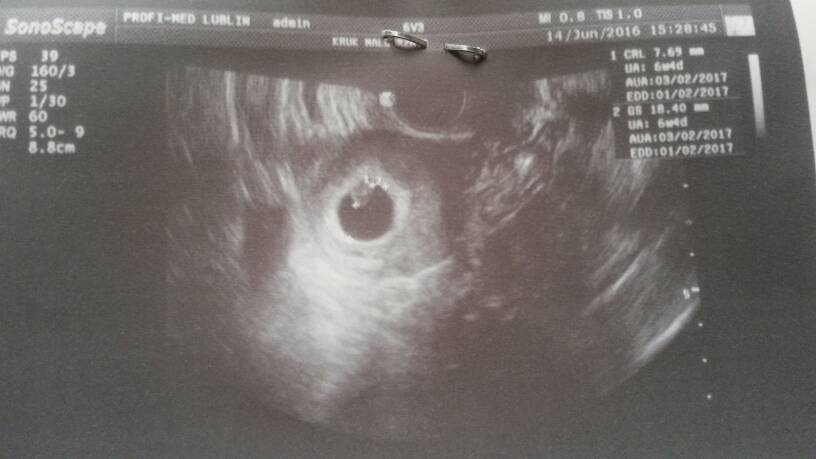

Wow super że już widać fasolkęJestem dziewczynywszystko dobrze. Ciąża niezagrozona, maleństwo ma 7,7mm serduszko ładnie bije. Wychodzi mi 6t4d i termin na 3 luty

Jest mały człowiek ! Serduszko bije, wszystko git ; ) Wg usg to 6t1d![]()